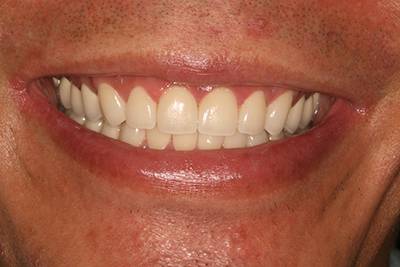

6. Eset

Nagymértékű fogkopás, erózió, csikorgatás a teljes rágóapparátust túlterhelve okoz reménytelennek tűnő helyzeteket.

Ebben az esetben implantátumok , koronák és hidak segítségével változtattunk a páciens fogainak érintkezésén. 6 hónapig ideiglenes hidakkal teszteltük a megváltoztatott harapási pozíciót. Ezután készültek el a végleges fix pótlások.